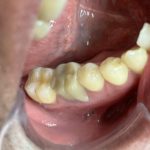

奥歯に白い歯をいれたい!という男性のお客様。半年前に高額を支払うものすぐに割れてしまった💦という方です、拝見致しましたところかなり食いしばりが強かったので裏打ちをメタルにしてみました❤️👍👍

なんでも食べていただいて大丈夫!綺麗な白いセラミックの奥歯にご満足していただきました。お口の中でお悩みの方はどうぞご相談ください。